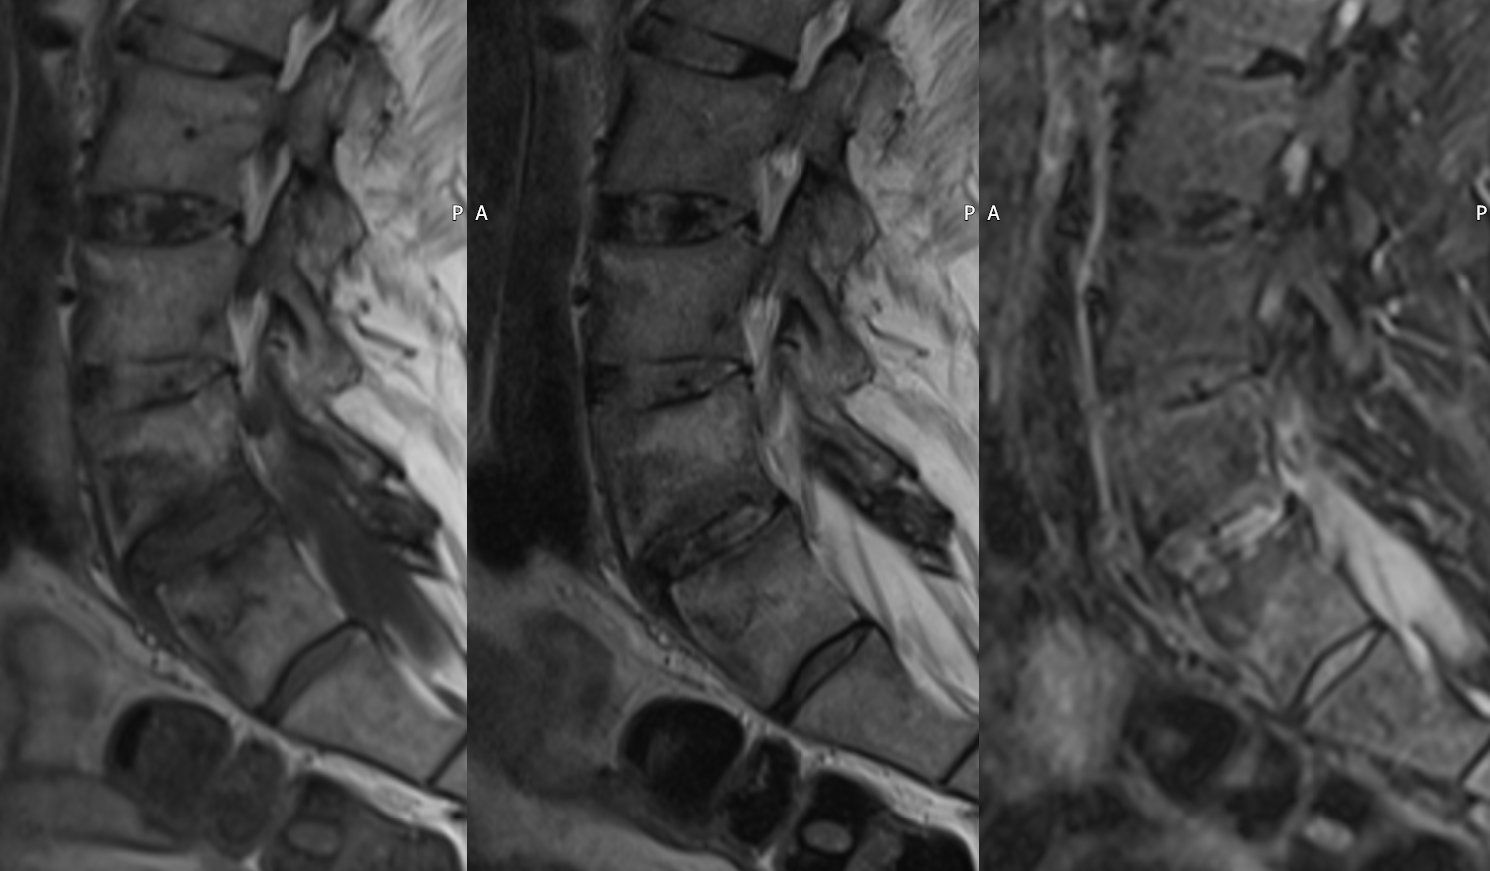

Andersson lesion in ankylosing spondylitis

Signs of ankylosing spondylitis and L4/L5 irregular, sclerotic endplates changes are seen. Minor anterior slipping of L5 vertebral body is olso detected according to instability. Note the gross lower lumbar facet osteoarthritis. |

T1w, T2w, T2w STIR Sag: The L4/L5 disc is hypointense on T1 weighted and hyperintense on STIR images. Often linear hyperintensities can be noted between the anulus fibrosus and nucleus pulposus. This signal change refer to disc related inflammation due to spondylarthritis. |